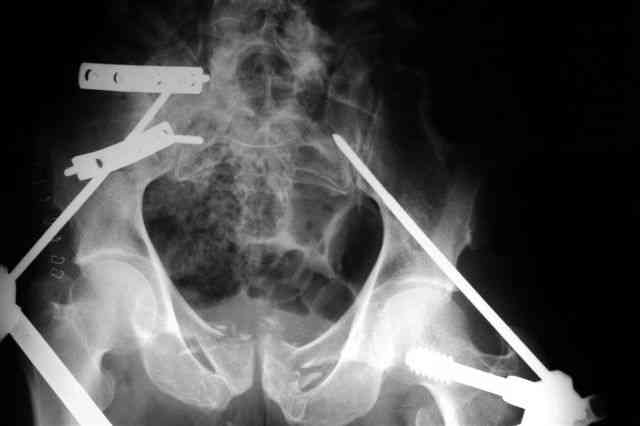

Вчера прооперировал больного.

Попытка низвести половину таза на тракционном столе ( скелетное вытяжение за бедро) безуспешная.

из переднего доступа добрался до правого КП сочленения , все запаяно костью, с помощью 2 шанцев винтов в крестец и подвздошную кость и элеватора репозиция, контроль ЭОП

и двумя пластинами фиксация.

Спереди, аппарат как рекомендовал Джолдас.

Снимки плохого качества( очень темные) завтра переделают и пришлю на конференцию.

На мой взгляд, смещение устранено и фиксация выглядит вполне анатомичной.